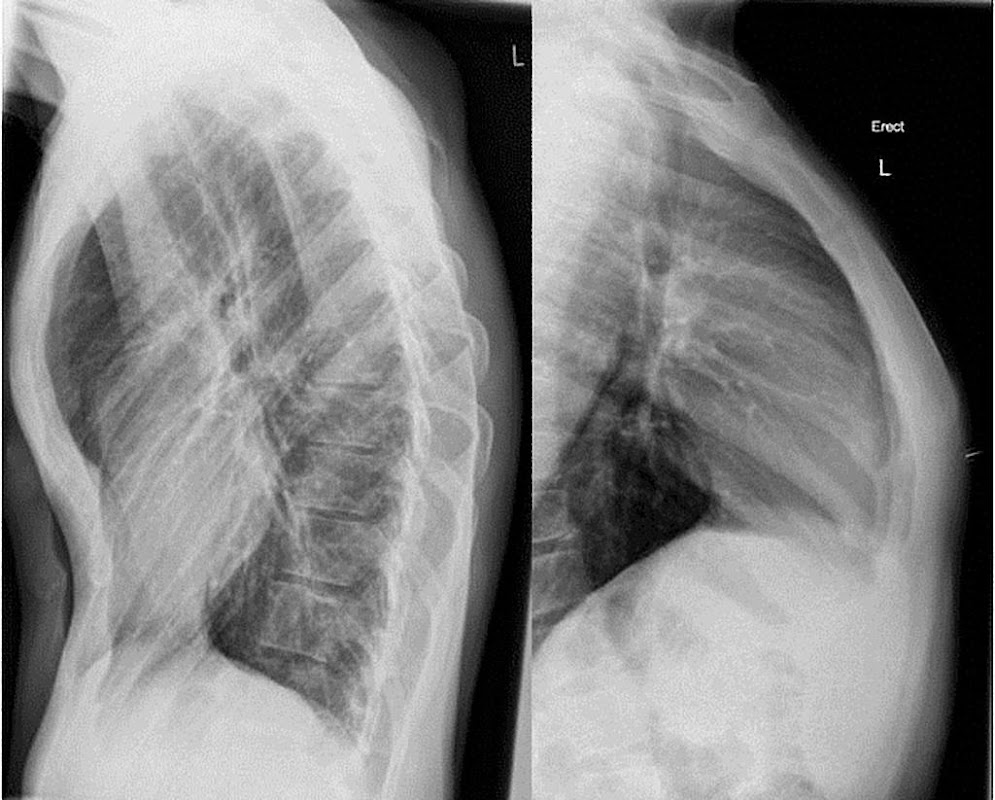

Perform a simulation of X-ray scanner (Prank). Thanks to the camera you can create the effect of X-ray vision of parts of your body such as the hand or foot.

X-ray camera is a simulation game that allows you to make a ray scan as if it were a real one in order to see the bones of a part of your body instantly using your rear camera. Download for free and enjoy the app with your friends and family during this holiday season.

(This application is NOT a REAL X-RAY CAMERA.) This application only gets an effect (SIMULATED) of vision on the screen of your device making use of the camera). (It is designed to make jokes to your friends and take screenshots with the X-ray vision effect (SIMULATED).